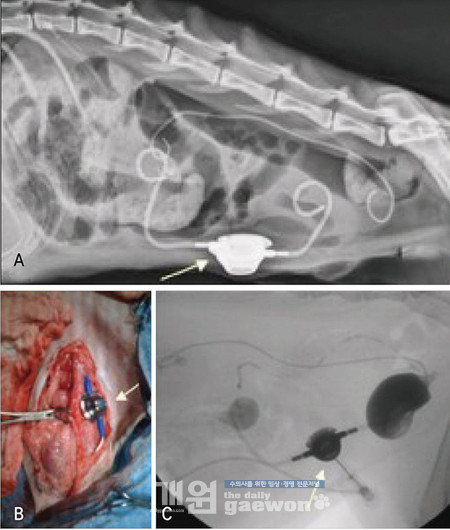

SUB는 신장과 방광을 연결하는 bypass 입니다(그림 2);A는 한쪽 신장은 SUB를 실시하였고, 반대편은 ureteral stent를 장착 하였습니다.

B는 중간의 port 라는 부분으로써 신장 카테터와 방광 카테터가 만나고 있습니다.

C에서는 이 port를 이용하여 urinary system의 patency를 확인하고 있는 영상입니다.